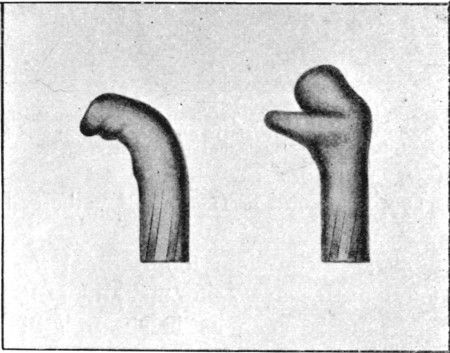

PLATES

1. Section of Mauser Aperture of Entry To face p. 73

2. Section of Mauser Aperture of Exit 76

16. Entry and Exit Mauser Wounds56

25a. Sections of Mauser Entry and Exit Wounds74